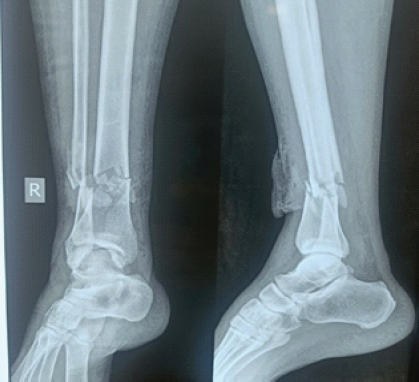

Harnessing 3D Printing Technology for Complex Acetabular Reconstruction in Revision Total Hip Arthroplasty: From Childhood Hip Trauma to Customized Modern Solutions